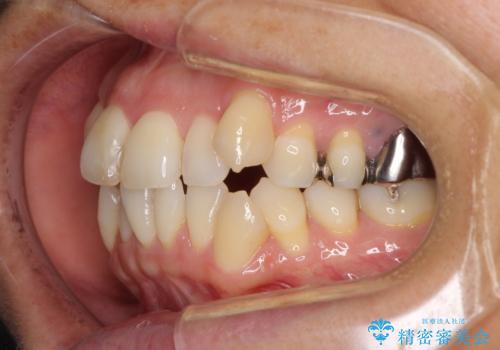

- 八重歯と、それによる口元の膨らみを気にして来院された患者様です。

八重歯・デコボコの解消とともに、前方に張り出した上顎前歯を引っ込めることを目的とし、上下左右の第一小臼歯4歯を抜歯をしてワイヤー矯正により治療することとしました。